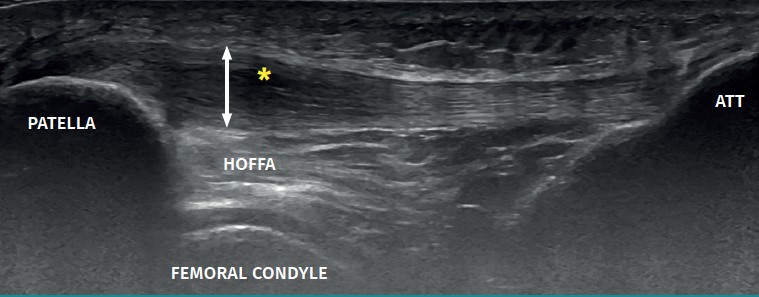

A continuación, verás un corte longitudinal del tendón rotuliano, desde la rótula (izquierda) hasta la tuberosidad tibial anterior (derecha).

El asterisco señala una zona claramente más oscura que el resto, donde el tendón ha perdido su estructura fibrilar normal. La doble flecha muestra un engrosamiento de 8,5 mm en sentido anteroposterior.